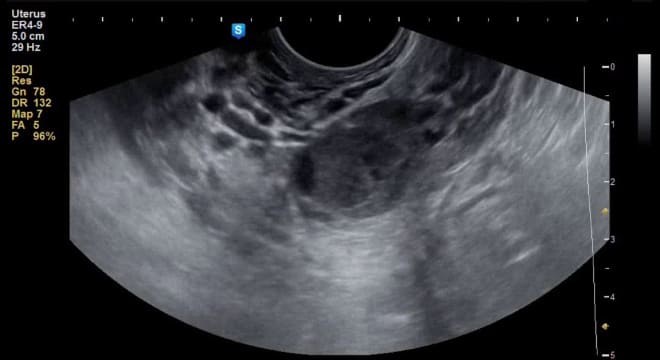

При наличии синдрома поликистозных яичников (СПКЯ) ультразвуковое исследование позволяет выявить как минимум 10 фолликулов, которые располагаются в виде ожерелья из жемчуга.

В случае развития данной патологии парные половые железы увеличиваются в объеме. УЗИ у пациенток с поликистозом показывает наличие не менее 10 патологических образований в придатках, каждое из которых достигает размера 1 см.